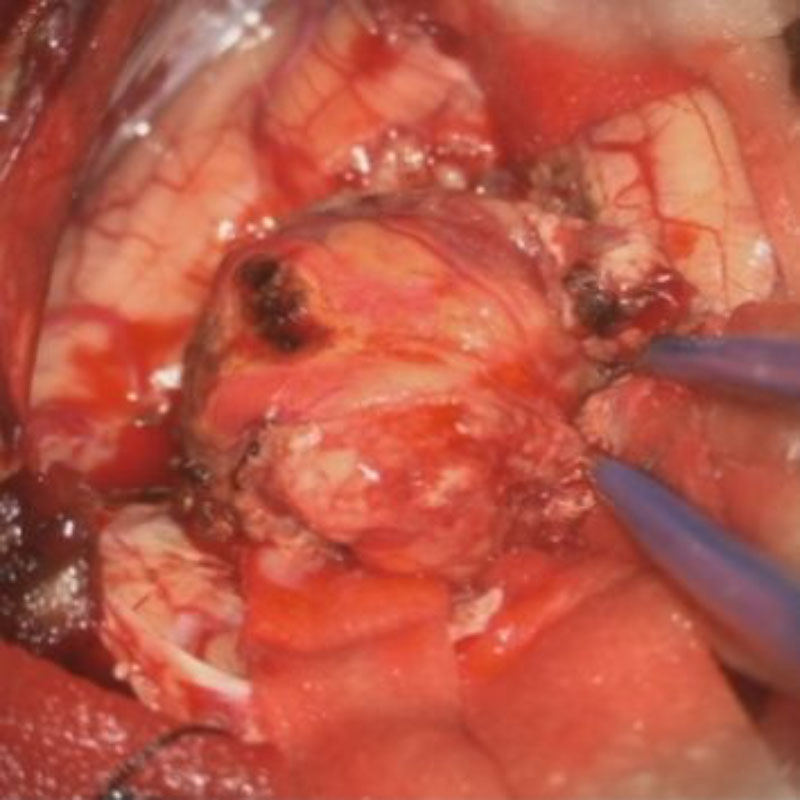

術中写真

摘出 前

摘出 中

摘出 後